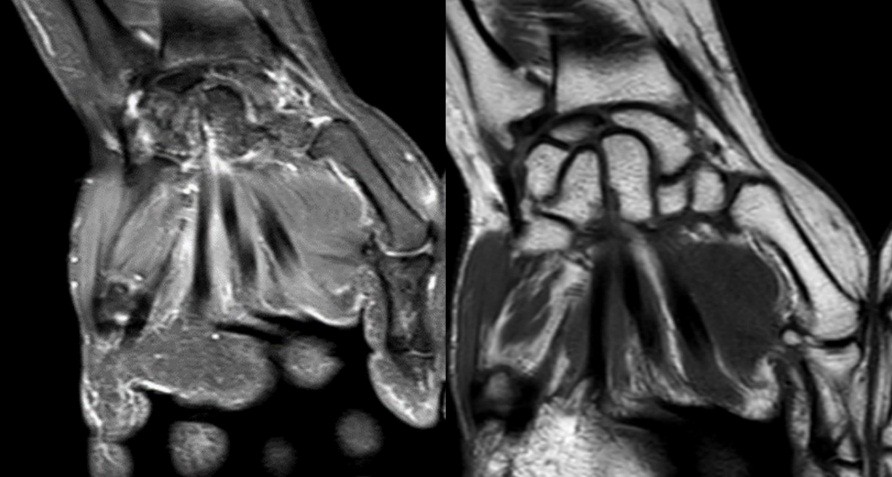

Here, we present two cases of Kienböck’s disease classified as Lichtman stage IIIc, characterized by complete osteonecrosis and a coronal fracture of the lunate, without associated cartilage damage. Both patients underwent a medial closing wedge osteotomy of the radius combined with compression screw fixation of the lunate fracture. The two patients were female, aged 42 and 47 years, with a history of wrist pain. Pre-operative imaging included standard wrist radiography, which revealed a negative ulnar variance (radiographic ulnar index), computed tomography (CT) confirming the presence of a lunate fracture, and MRI demonstrating osteonecrosis (showing a hypointense signal on T1-weighted sequences and a hyperintense signal on T2-weighted sequences, with no gadolinium enhancement). No signs of carpal instability or cartilage degeneration were observed in the surrounding structures.

- Patient B: A 47-year-old left-handed housewife presented with a 1-year history of left wrist pain. She reported no history of trauma, was a non-smoker, and had no significant medical history (Fig. 4, 5, 6).

Figure 4: X-ray radiographic ulnar index of −3.7 mm.

Figure 5: Computed tomography scan.

Figure 6: Magnetic resonance imaging.